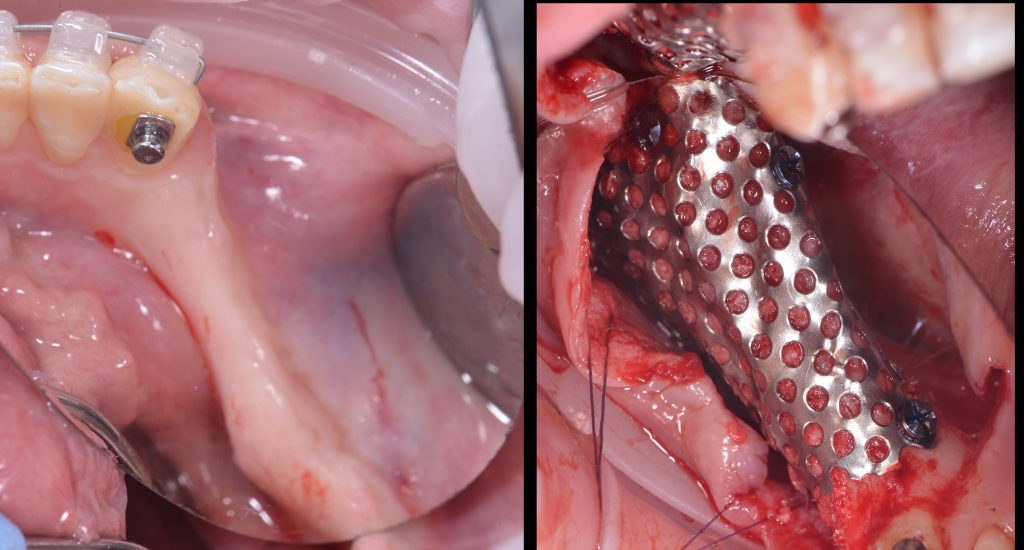

Based on these models, stereolithographic models were produced to plan the placement of the titanium mesh and ensure its accurate fit